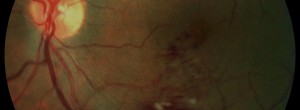

Retinal vein occlusions.

GAIN. Characterization of geographic atrophy progression in patients with age-related macular degeneration: evolution and risk factors associated with geographic atrophy progression